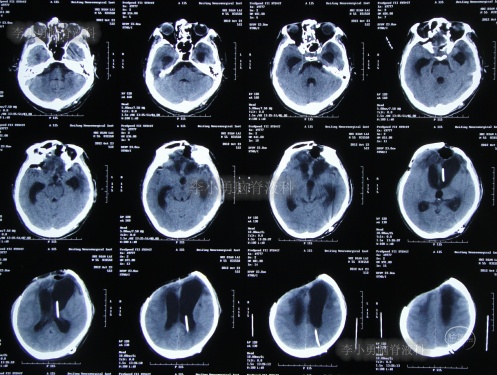

2013年1月14日(入院治疗75天),进行了左侧脑室腹腔分流术(图-11);

图-11:2013年1月14日术后头颅CT

2013年1月17日(入院治疗78天),晚上19点左右,患者突发意识障碍、右侧肢体偏瘫,头部外引流管流出粉红色液体,急查头颅CT示左额颞顶区硬膜下血肿,蛛网膜下腔出血(图-12)。于当晚急诊全麻下进行“左额颞顶硬膜下血肿清除术”。

图-12:2013年1月17日头颅CT

术后患者仍处于昏迷状态;次日2013年1月18日晨起,颅骨缺损处张力较高,复查头颅CT示术区无明显再出血,左顶叶硬膜外血肿,术区脑组织肿胀(图-13),当天进行了左额颞顶硬膜下血肿清除术后,左顶叶硬膜外血肿(图-14)。

图-13:2013年1月18日头颅CT

图-14:2013年1月18日术后头颅CT

2013年1月22日(入院治疗83天),患者术区引流管引流液极少,复查头颅CT脑室较前稍有扩张,右侧骨窗张力仍较高(图-15),进行了侧脑室外引流术(右)+左额颞顶硬膜下引流管去除术+左顶硬膜外引流管去除术。

图-15:2013年1月22日头颅CT